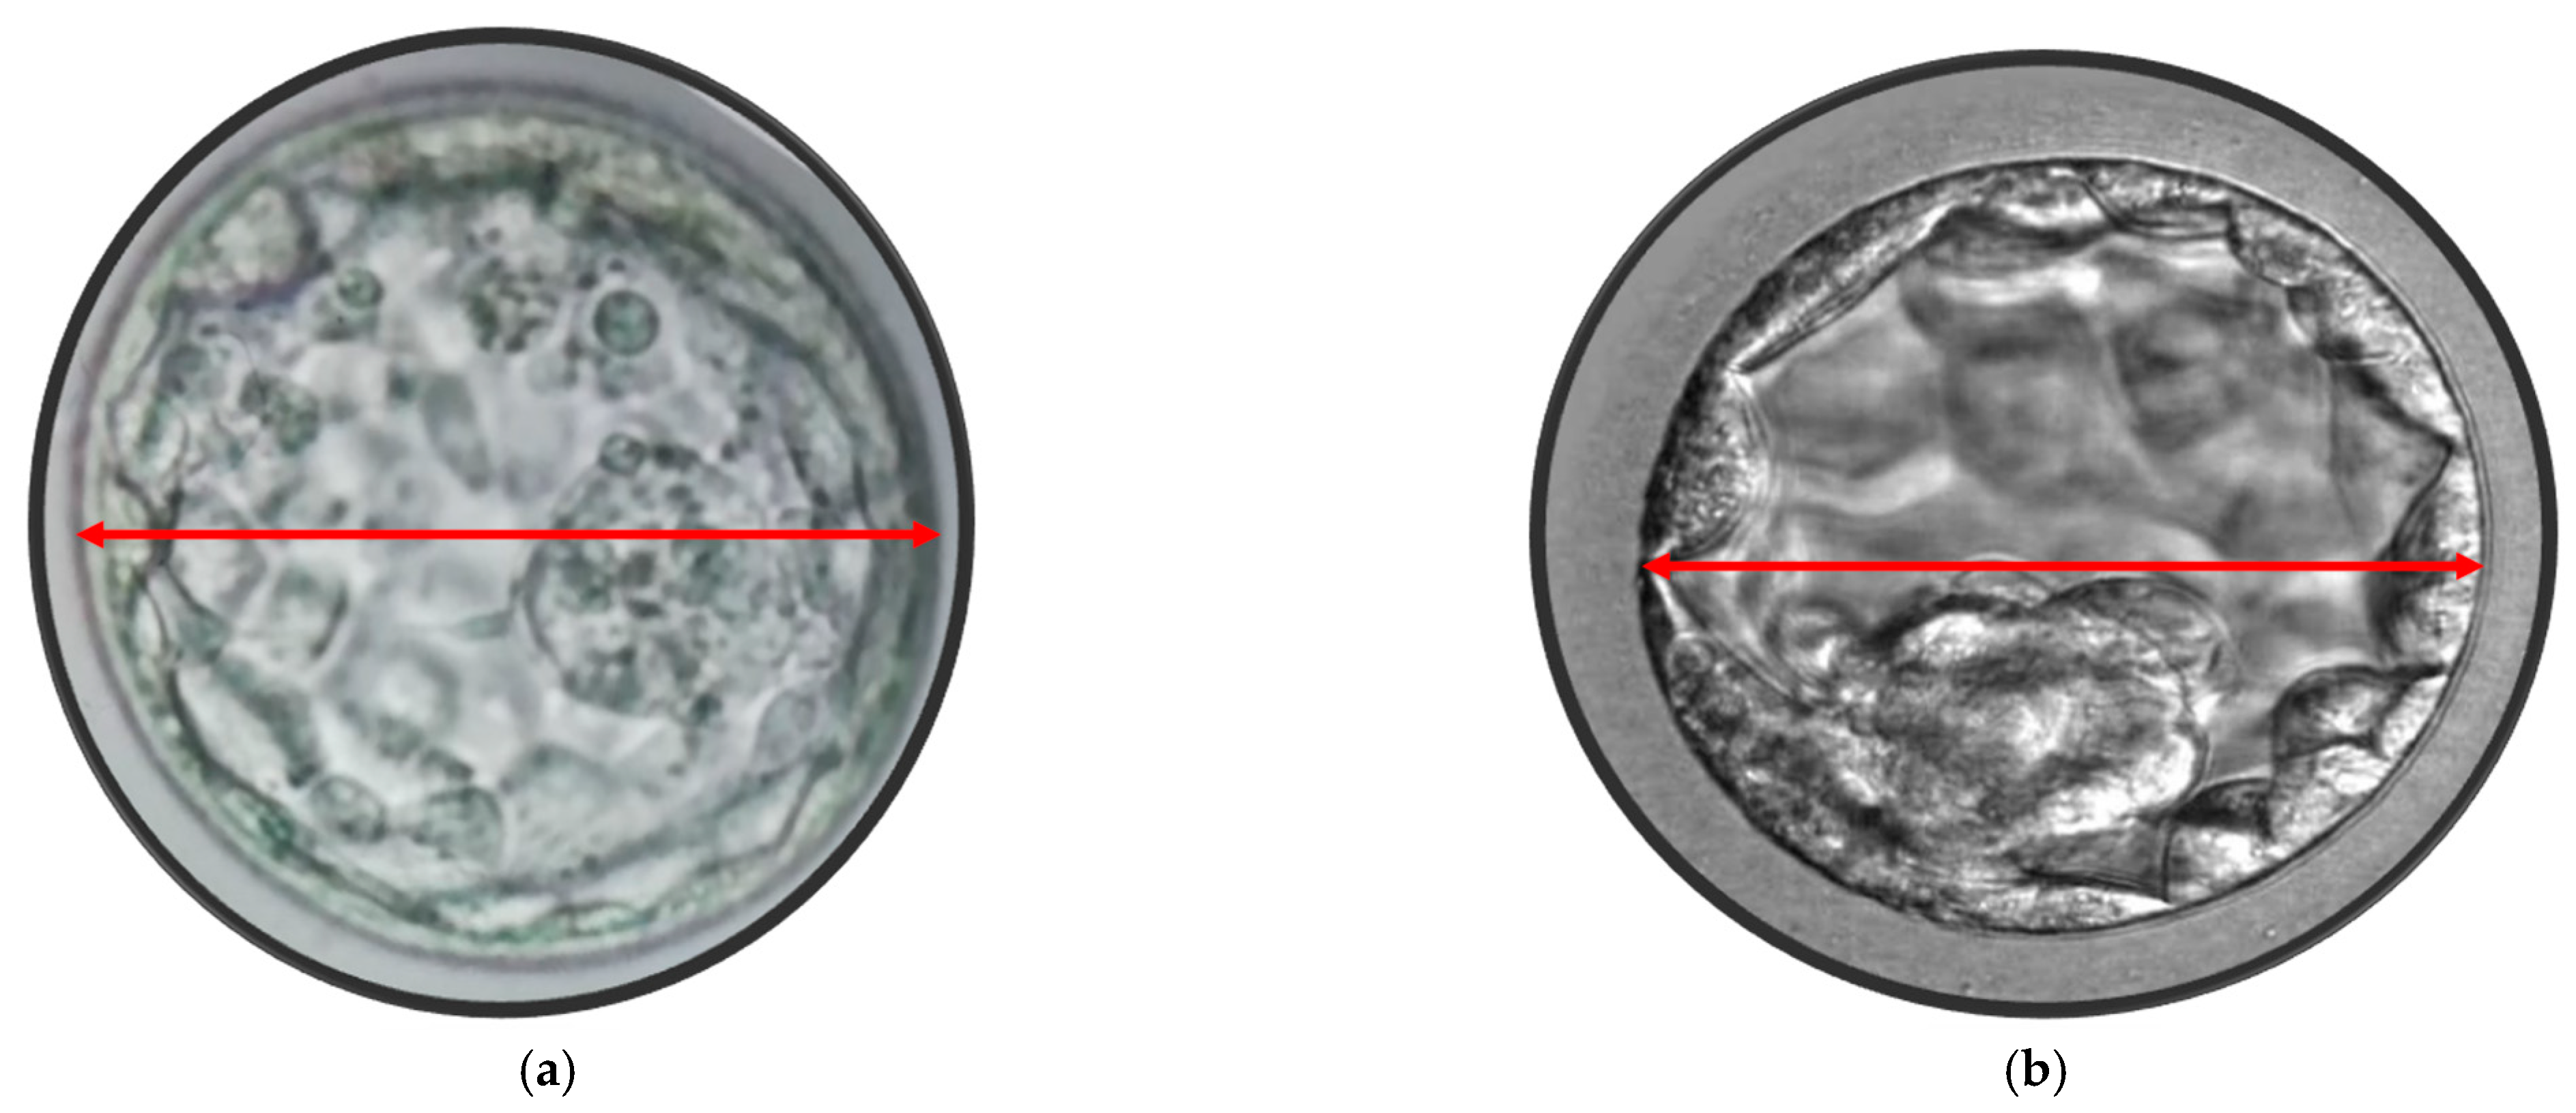

After five days of development, human embryos reach the blastocyst stage, which consists of two differentiated cell types: the ICM and TE cells. In this study, blastocyst evaluation was based on the degree of the blastocoel cavity expansion, as well as the quality and cohesion of ICM and TE, following the Gardner’s scoring system [31]. Only blastocysts with a score ≥ 2, excluding those graded as CC, were selected for eSBT or cryopreservation. On the morning of day 5, before the embryo transfer, approximately 110–116 h after ICSI, morphometric assessments of all blastocysts were performed at 400× magnification using an inverted microscope (IX71, Olympus, Tokyo, Japan). Three digital images were captured for each blastocyst using Chronos software with a CCD camera (CS230B, Olympus, Tokyo, Japan). One image focused on the equatorial plane of the blastocyst, while the other two focused on the TE cells at the top and bottom of the blastocyst. Blastocyst measurements were taken using a straight line or a polygon tool using a software (Image J software, Version 1.6, USA). The blastocyst diameter was determined as the average of two perpendicular diameters in the equatorial plane. The blastocyst area was measured by outlining the entire blastocyst with the polygon tool in the software, as described by others [16,17,18,19]. These measurements were taken from the outer borders of the TE, excluding the area occupied by the zona pellucida (Figure 1 and Figure 2). Measurements were recorded for each transferred blastocyst, and the data were analyzed in relation to the CPR. All the measurements were performed by the same embryologist (RS). None of the parameters analyzed, including age, number of oocytes collected, BMI, endometrial thickness, cause and duration of infertility, showed any differences between the groups categorized by blastocyst diameter (≥170 µm versus <170 µm) or blastocyst area (≥25,000 µm2 versus <25,000 µm2).

Figure 1.

(a) Blastocyst area 33,549 μm2. (b) Blastocyst area 19,704 μm2.

Figure 2.

(a) Blastocyst maximum diameter 178 μm. (b) Blastocyst maximum width 148 μm.